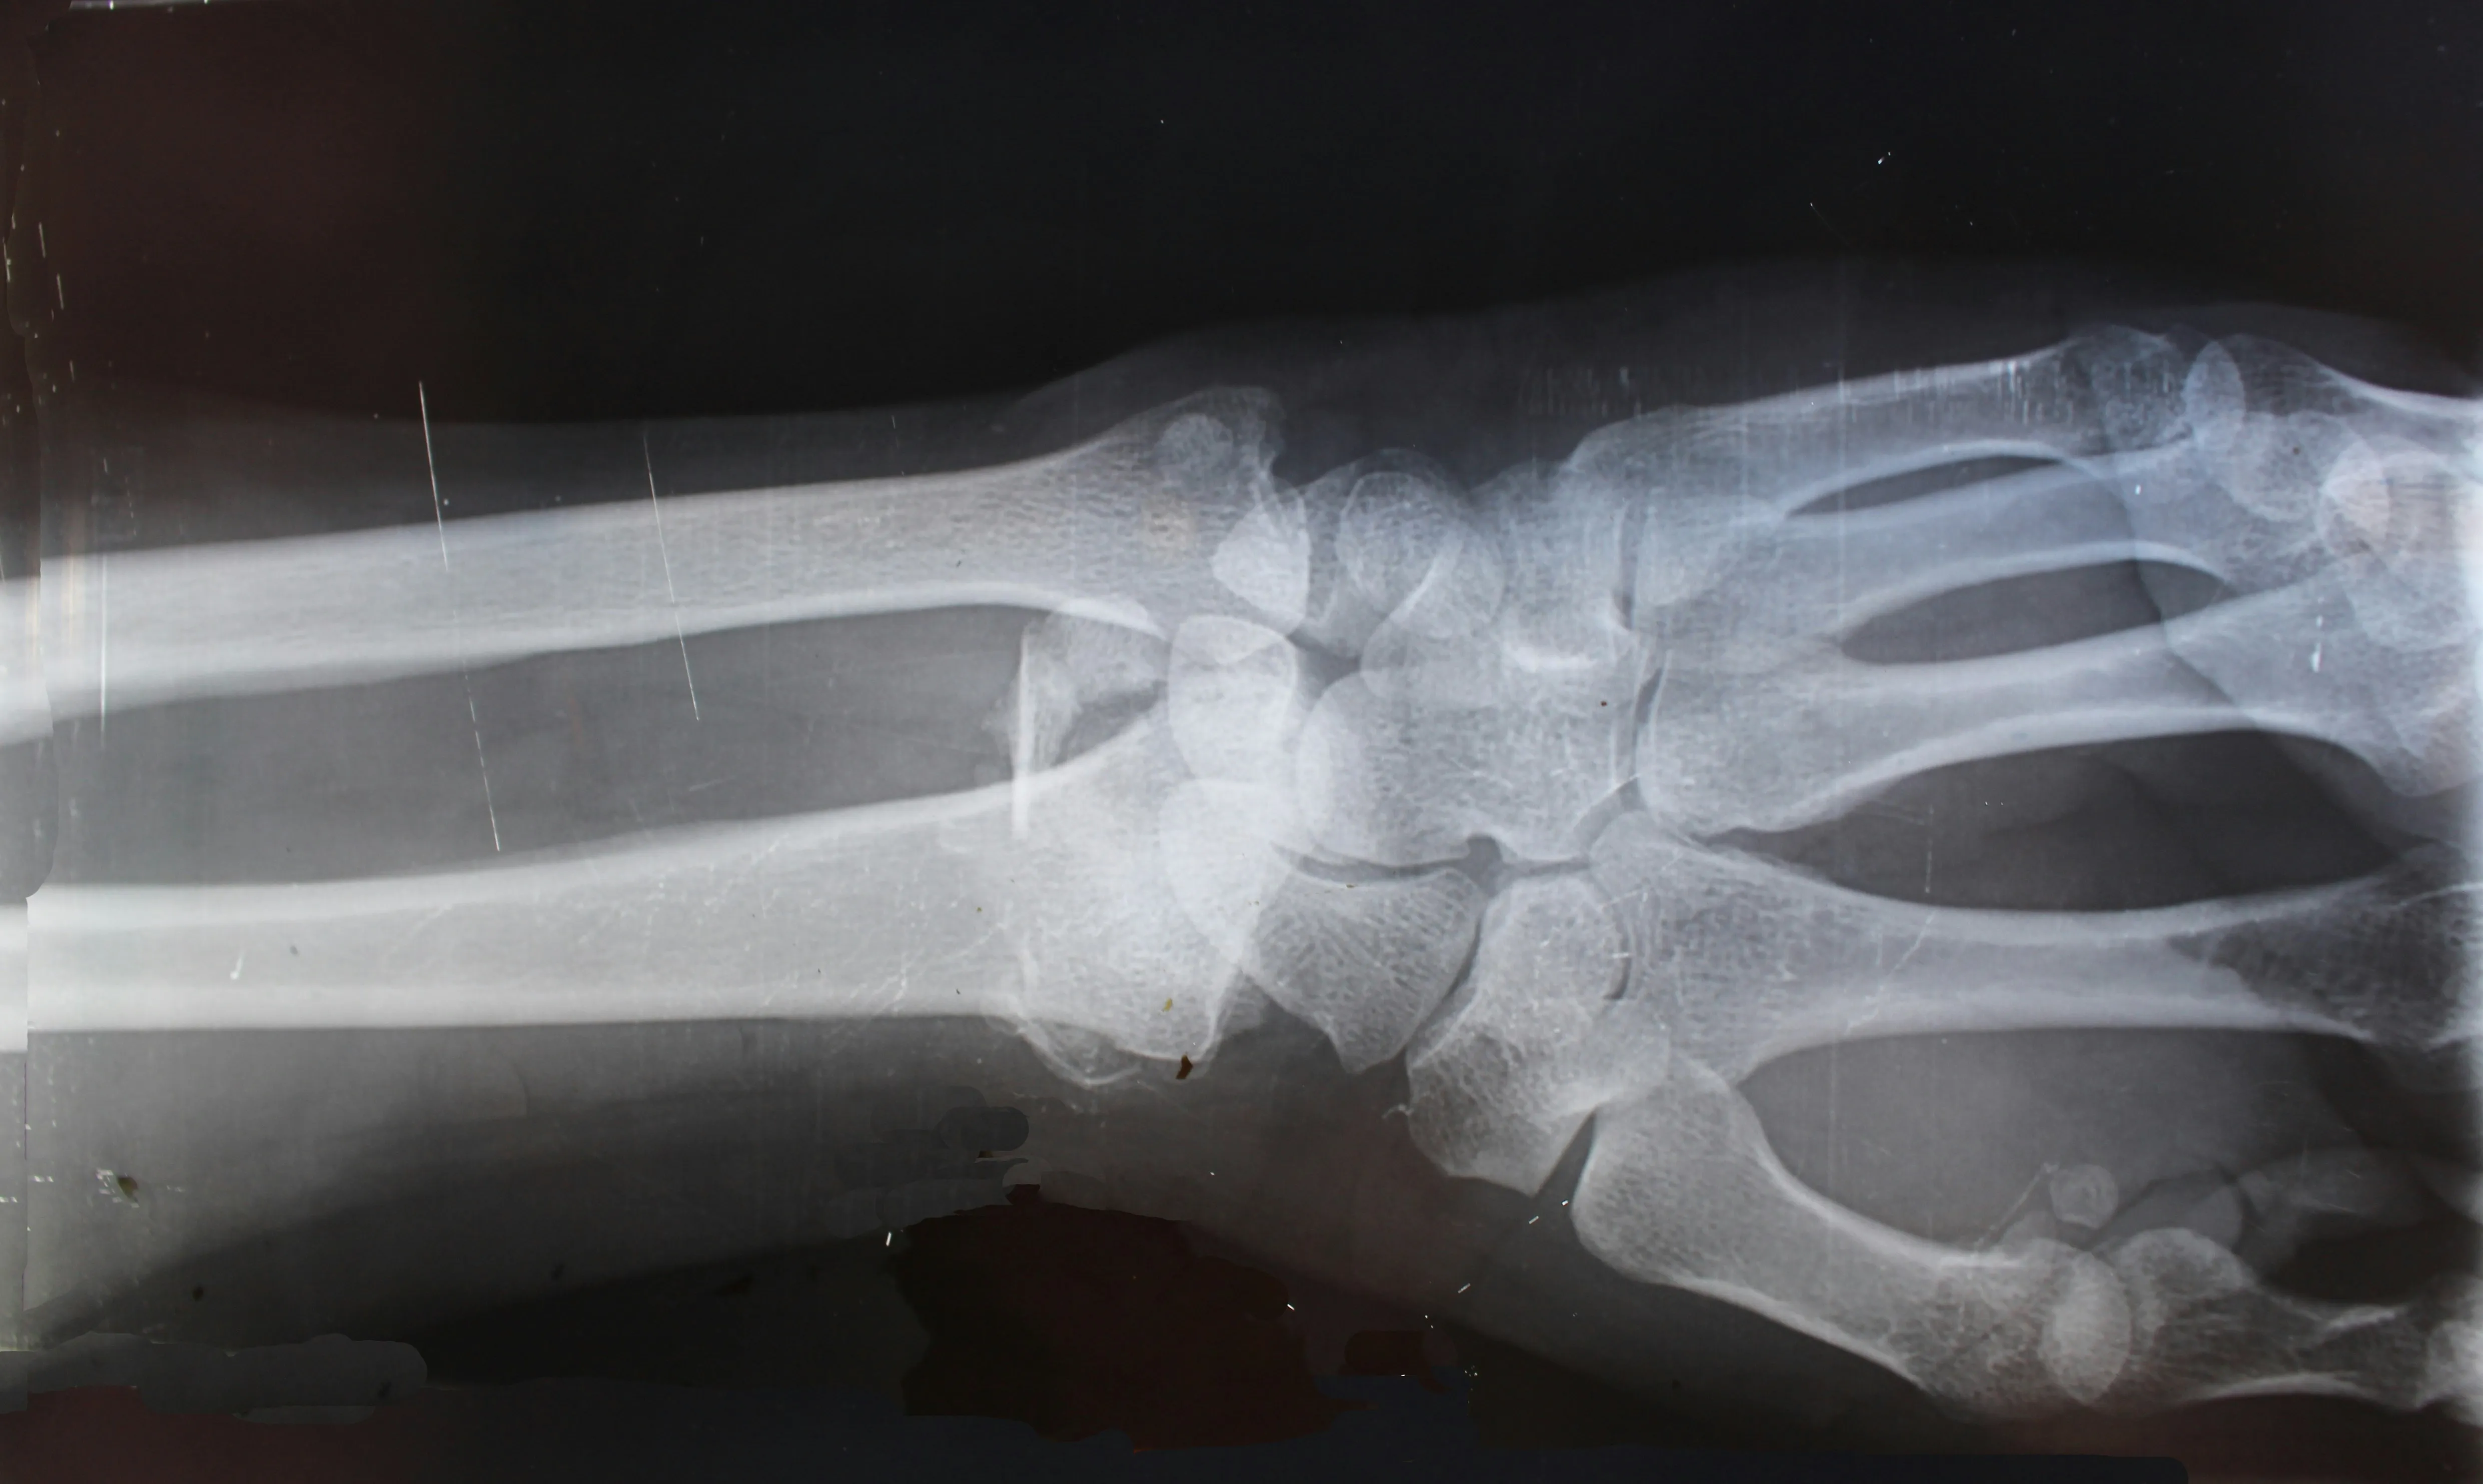

Radiografía detallada mostrando estructura ósea

Radiografía detallada de muñeca mostrando estructura ósea